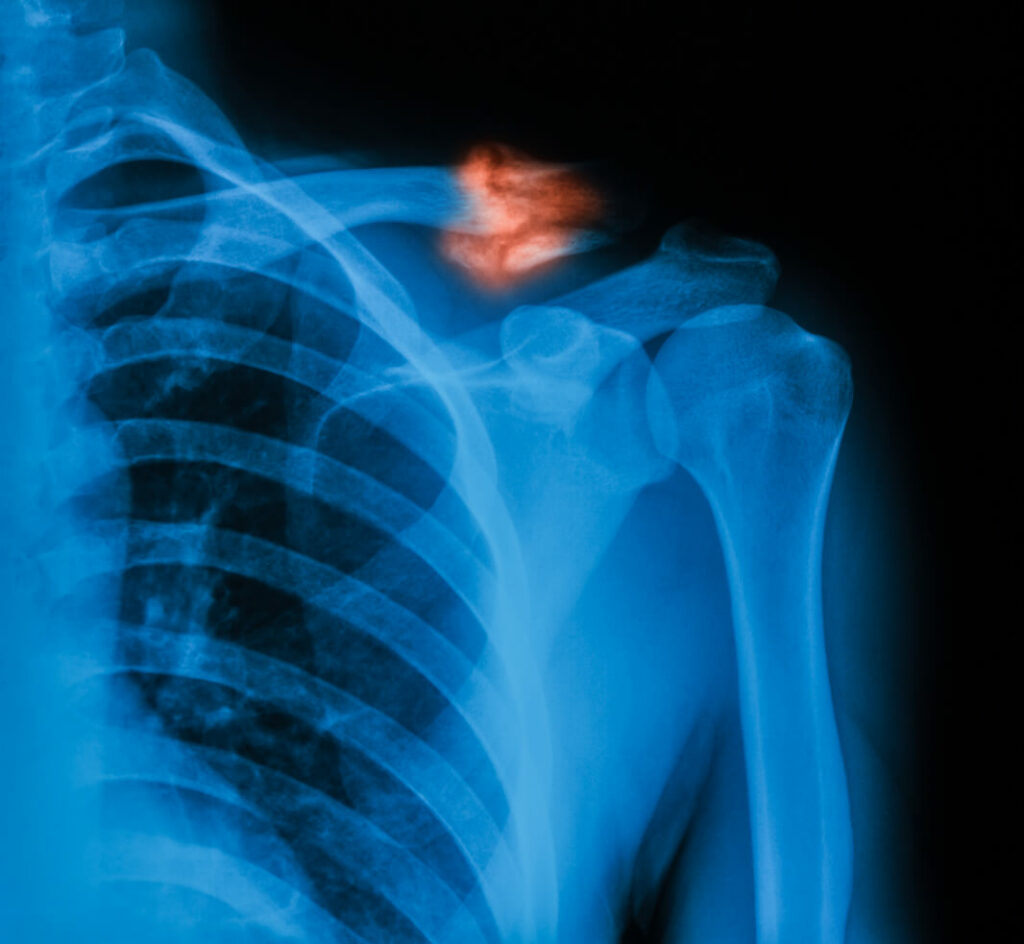

Diagnosis of a Broken Collarbone

When you visit an orthopedic surgeon, the doctor will perform a physical examination to assess the severity of your injury. Imaging tests like X-rays or CT scans help confirm the location and extent of a fracture.